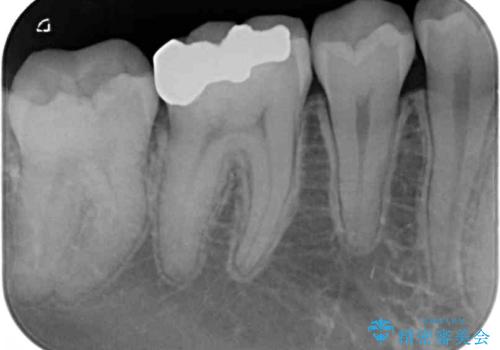

- 矯正治療後に目立つ銀歯を白くしたいとのことで来院された患者様です。

右下の銀の詰め物は、外してむし歯を除去した後、セラミックインレーにて修復することとしました。

左上の銀歯は、銀歯の下に金属の土台が入っているため、その土台を除去し、ファイバーコアにやり替えて、オールセラミッククラウンにて補綴することとしました。